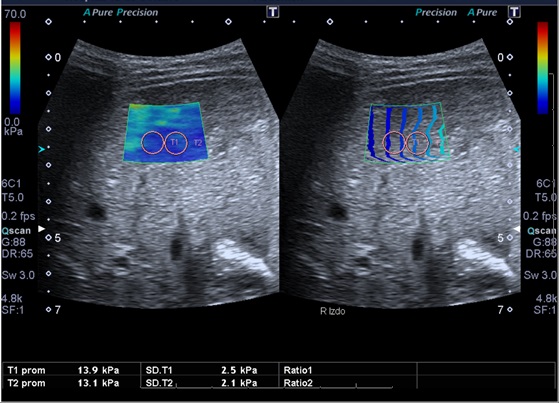

Tras el diagnóstico de síndrome de Joubert, se inició seguimiento multidisciplinar del paciente. Durante el seguimiento posterior, a los 10 años de edad, se detecta en control analítico una hipertransaminasemia creciente con patrón de colestasis sin hiperbilirrubinemia, y con tendencia a la trombopenia. Se deriva a consultas de Gastroenterología del hospital terciario de referencia, para proceder a un despistaje de hipertensión portal. En dicho centro, como primera etapa, se solicitó ecografía abdominal con Doppler y elastografía hepática. Ambas pruebas muestran alteraciones. De especial valor resulta la elastografía, en la que se objetivan unos valores compatibles con aumentado del grado de rigidez (de media, 15,8 kPa) (Figs. 1 y 2). En la ecografía Doppler se constató una hepatomegalia leve, sin alteraciones significativas de los flujos sanguíneos a través de la vena porta, arteria hepática y venas suprahepáticas.

En estos pacientes es importante evaluar, como primer paso, la realización de elastografía hepática, para estimar la rigidez el hígado y, por consiguiente, si puede existir fibrosis o no.

Los grados de fibrosis se dividen en cinco, siendo F0 equivalente a hígado sano y F4, máxima fibrosis o cirrosis. El resultado de la elastografía se expresa en kilopascales (kPa), y se correlaciona con los grados de fibrosis (F0-F4). El rango de equivalencias varía en función del tipo de elastografía que se realice, por lo que estos valores no son comparables entre técnicas elastográficas distintas, pero si el grado de fibrosis en que se clasifiquen1,2,3,4,56. Se trata de una técnica radiológica sencilla y no invasiva, que nos permitirá realizar una monitorización del hígado, permitiendo repetirla periódicamente al tratarse de una exploración segura para el paciente. No obstante, hay que recalcar que el “patrón oro” diagnóstico de la fibrosis hepática es la biopsia.